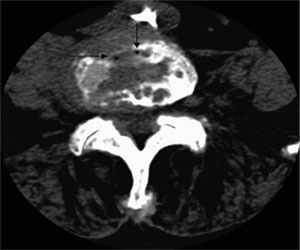

تصاویر CT Scan سوزن در محل دیسک بین مهره ای:

با کمک تصویربرداری همزمان CT Scan و مشاهده سوزن در تمام طول مدت تزریق، آسیب دیدن ساختار های مجارو مانند شریان و ورید های ناحیه (که می تواند باعث خونریزی خود محدود شونده شود)، آسیب دیدن احشا داخل لگنی مانند رحم و یا آسیب دیدن اعصاب نخاعی و دیسک های بین مهره ای به ندرت اتفاق می افتد و می توان از این گونه عوارض جلوگیری کرد. دیگر عارضه احتمالی این تزریق افزایش درد موقتی است که در بعضی از بیماران اتفاق می افتد و به دلیل ورود سوزن به بافت است و خود به خود بهبود پیدا می کند. عفونت محل تزریق به ندرت و اکثرا در بیماران با نقص سیستم ایمنی (دیابت، سرطان، ...) اتفاق می افتد و به دلیل انجام پروسیجر به صورت استریل نادر است.